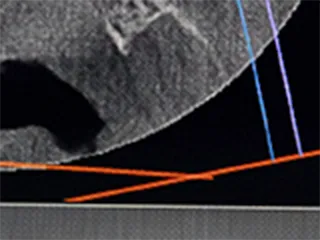

根管は一人ひとり形が違い、弯曲や側枝と呼ばれる入り組んだ構造も含まれており、どのような構造になっているかを正確に把握した上で、神経を精緻に処理をすることが重要です。

歯科用コーンビームCTを使用し、根管の内部を3次元的に解剖したように隅々まで構造を把握することで、歯髄を取る必要な部分がはっきり分かり、勘や経験に頼らず、的確に処置を進められます。

• 斜めからの図

斜めからの図

• 上からの図

上からの図

• 横からの図

横からの図